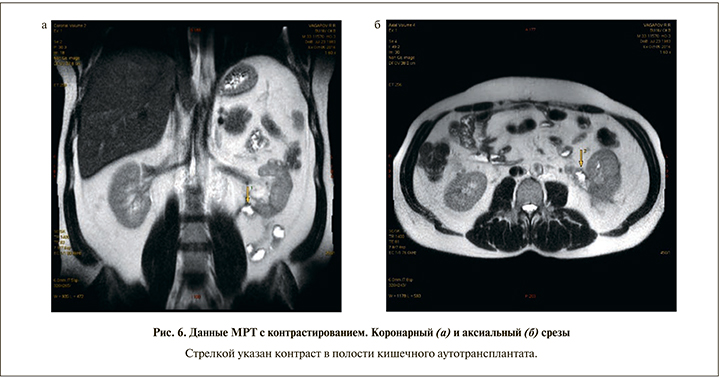

Ход операции. Под эндотрахеальным наркозом выполнена срединная лапаротомия. Рассечена брюшина по латеральному краю ободочной кишки, забрюшинная клетчатка по левому фланку деревянистой плотности с явлениями склероза. Мочеточник плохо дифференцировался, представлен рубцовым тяжом на всем протяжении. Левая почка несколько увеличена, мобилизована от паранефральной клетчатки, капсула рыхлая, под капсулой единичные апостемы (интраоперационная находка). Выполнена декапсуляция почки. Визуализирована лоханка, на уровне мочеточника – склероз. Лоханка рассечена на 1,2 см. Осуществлена мобилизация мочевого пузыря в ректовезикальном пространстве. Петля подвздошной кишки до 30 см мобилизована, отступя на 15 см от илеоцекального угла с сохранением сосудистой аркады, резецирована линейным степлером 30 мм. Непрерывность подвздошной кишки восстановлена формированием латеролатерального илеоилеоанастмоза в один ряд нитью ПДС 3/0. Изолированная петля подвздошной кишки перемещена в окне брыжейки сигмовидной кишки, расположена в изоперистальтическом направлении. Сформирован прямой пиелоилеоанастмоз непрерывным швом нитью Advantime 4/0. На заднюю губу анастомоза наложен дополнительный ряд швов. Дистальный конец подвздошного сегмента сформирован в виде конуса, наложен ручной однорядный илеоцистоанастмоз внебрюшинно, в подслизистом слое узловыми швами нитью Advantime 4/0 с дополнительной герметизацией мышечной частью стенки мочевого пузыря. Нефростомический дренаж установлен внебрюшинно и выведен в левой поясничной области. Поскольку полной герметизации нефростомы достичь не удалось (декапсуляция, рыхлая паренхима почки), через отдельные контрапертуры слева установлены улавливающие дренажи к пиелоилеоанастмозу и к цистоилеоанастмозу. Проведен контроль гемостаза, наложены послойные швы на рану. Асептическая наклейка. В послеоперационном периоде пациент получал антибиотикотерапию, прокинетическую, уросептическую терапию. Состояние постепенно улучшилось. Суточный диурез составил 1000–1200 мл. В течение 10 дней констатировали значительное отделяемое по улавливающим дренажам – от 160 до 300 мл в сутки, с постепенным снижением количества отделяемого. По нефростоме отделяемого ежесуточно до 60 мл мочи. Дренажи поэтапно удалены на 14-е сутки. Гипертермии не было. Контрольная КТ-фистулография выполнена 04.05.2016 (рис. 4): левая почка незначительно увеличена, вокруг почки отек паранефрия, чашечки умеренно расширены. 13.05.2016 выполнена МРТ с контрастом (рис. 5). В удовлетворительном состоянии в отсутствие жалоб, нормальной температуры тела и удовлетворительных лабораторных показателяей пациент выписан из отделения на 26-е сутки.

Осмотрен через 5 мес. после операции 05.10.2016. Состояние пациента удовлетворительное. Жалоб нет. Работает по специальности (мастер-нефтяник). При амбулаторно выполненном УЗИ от 04.10.2016: правая почка с конкрементом в средней чашечке до 0,7 см. Левая почка расположена несколько ниже нормы, контуры ровные, длина – 10 см, ширина – 6 см, толщина – 5 см. Толщина паренхимы – 1,8 см, эхогенность ее обычная, ЧЛС не расширена, в нижней чашечке конкремент до 0,7 см. Данные МРТ от 05.10.2016: ЧЛС не расширена, МР-признаки хронического пиелонефрита (рис. 6).

Желтой стрелкой указан контраст в полости кишечного аутотрансплантата.